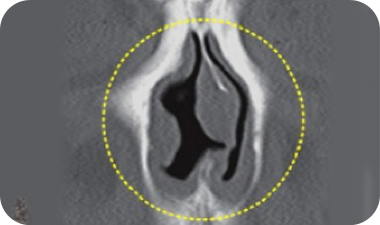

鼻瓣区狭窄症

所谓鼻瓣是指空气流动的鼻内部中,最为狭窄的部位。

由于本身就是相对狭窄的部位,所以当此部位因各种原因进一步变窄时,则被称为鼻瓣区狭窄症,鼻瓣区狭窄症会诱发鼻塞,睡眠障碍等问题。

鼻瓣区狭窄症 手术技术

为矫正变窄的鼻瓣区域,可采用于鼻中隔及其侧壁之间植入软骨,扩充鼻瓣区宽度的楔子植入术。

手术前狭窄的 鼻瓣

于鼻中隔软骨及鼻侧壁间 植入软骨

加宽鼻瓣部位 矫正鼻瓣区狭窄症